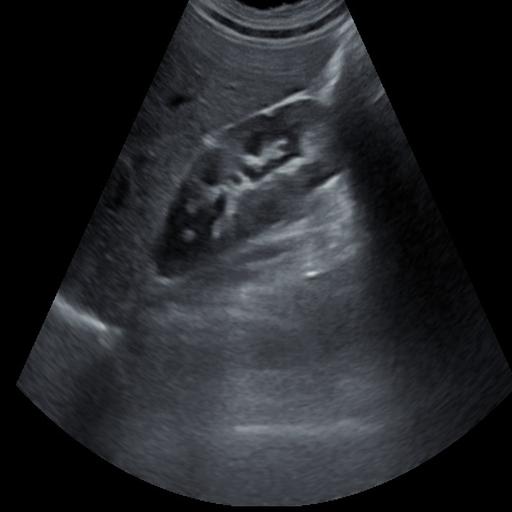

数据样例

结石肾脏样例